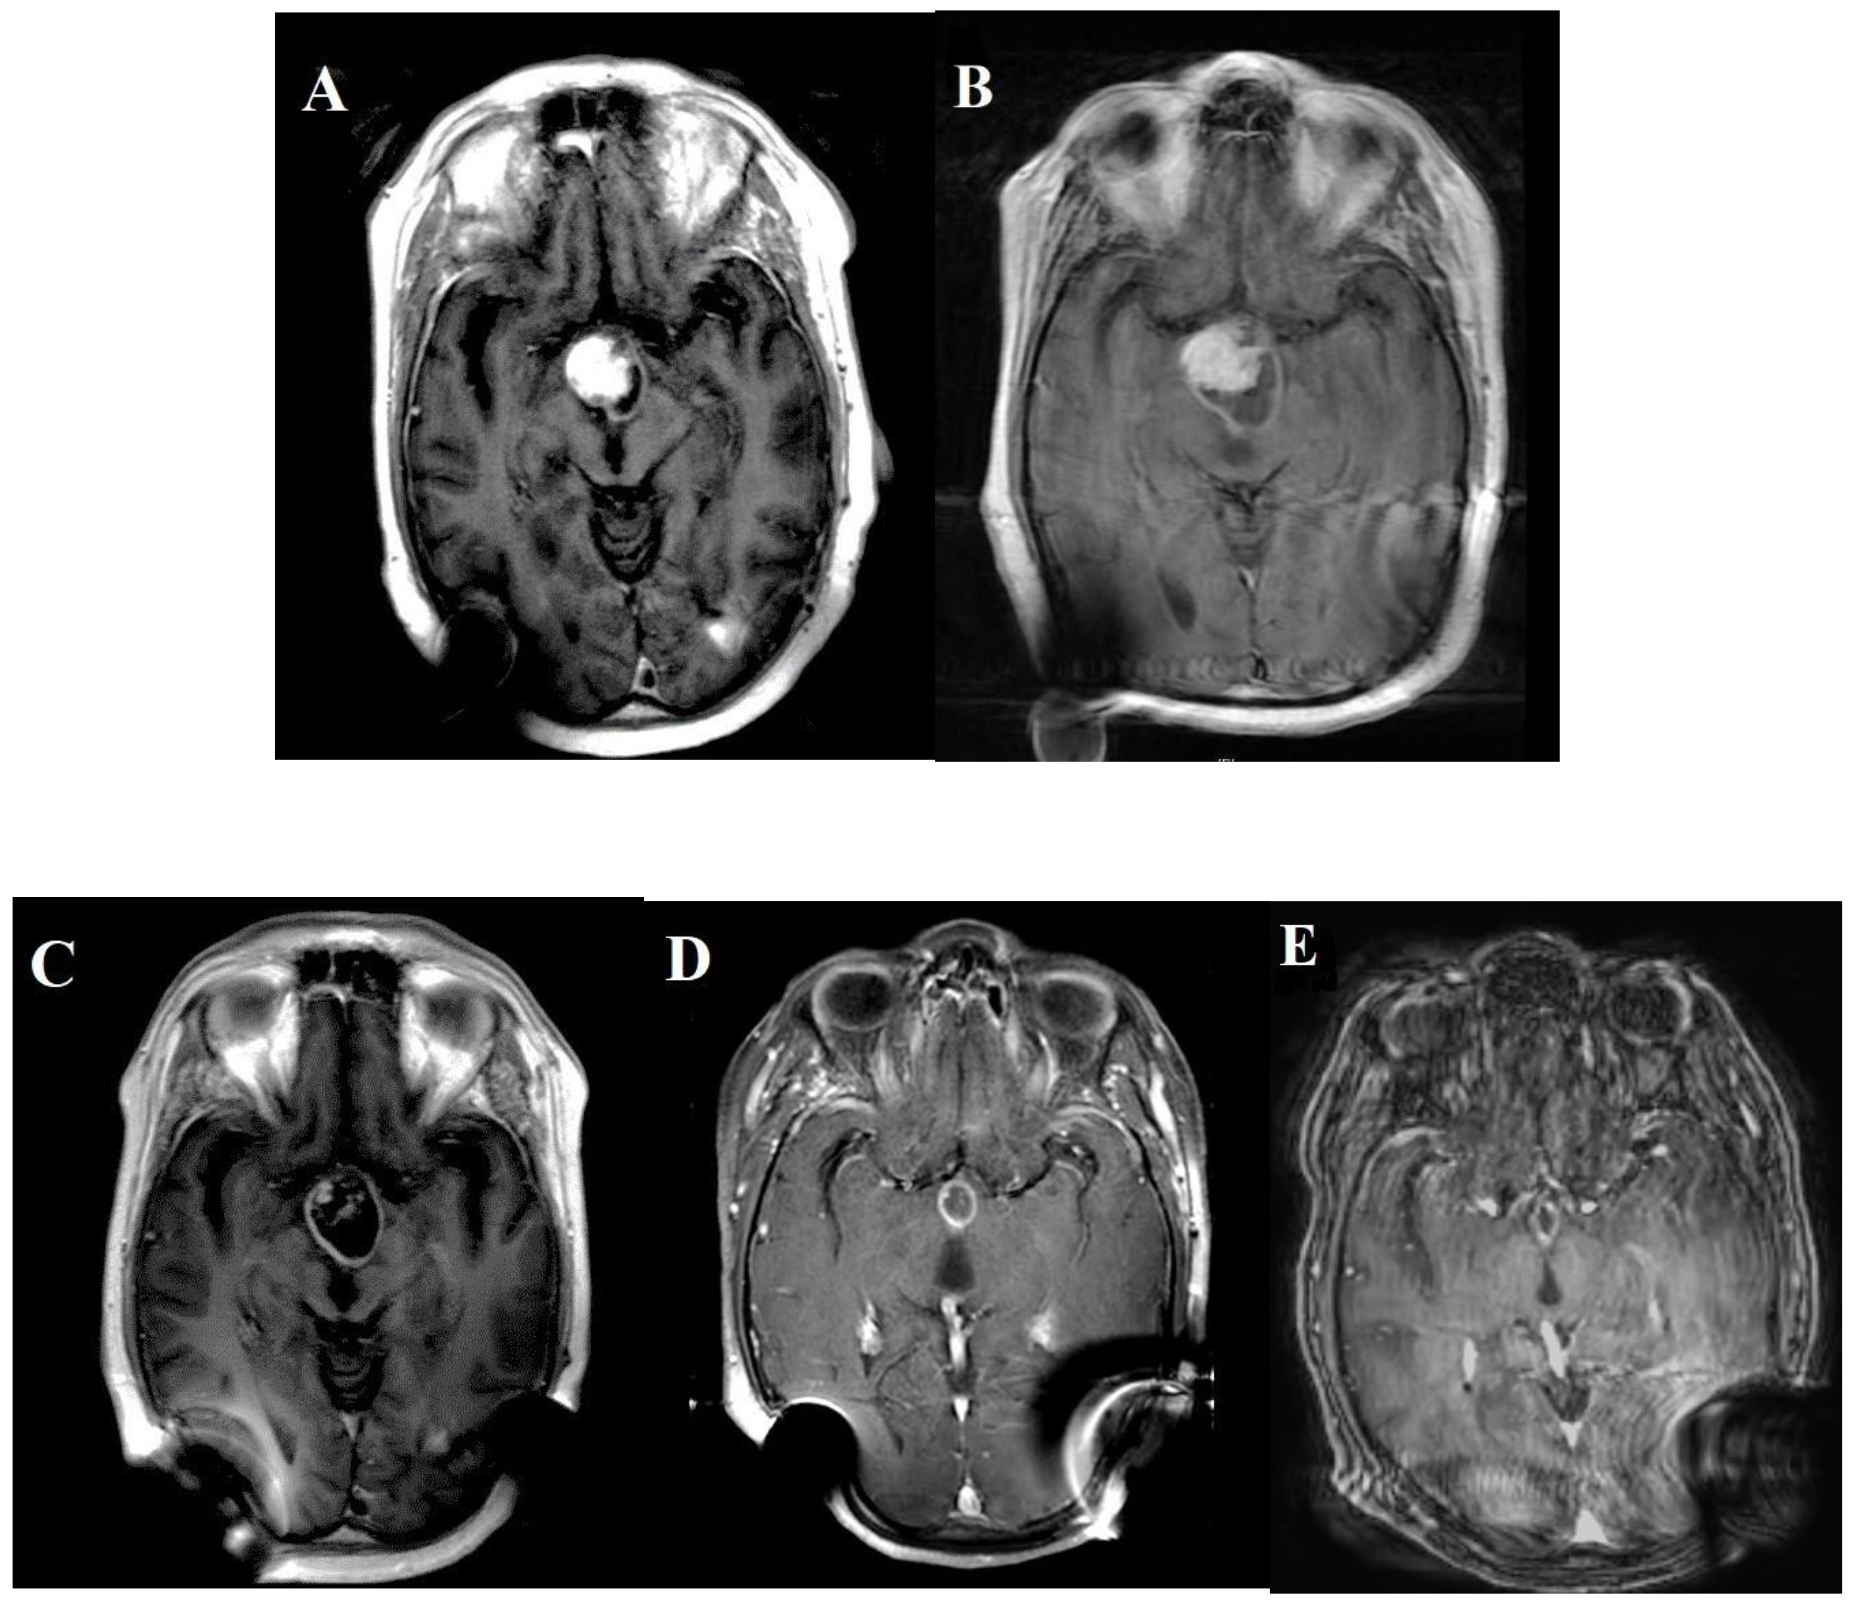

Post-operatively, the patient’s MRI brain demonstrated residual suprasellar craniopharyngioma (45 x 39 x 25 mm) with multiple cystic components (Figure 1A). Efforts to obtain Dabrafenib and Trametinib were unsuccessful and repeat MRI brain showed an increase in the size of cystic components (48 x 53 x 29 mm) with stable nodular disease and resolution of his hydrocephalus (Figure 1B). Clinically, the patient continued to improve in strength but had a significant disability with his cognitive status. He continued to take HRT, and his dexamethasone dose was reduced to 0.5 mg PO QD.

MRI brain before BRAF inhibitor was introduced (both A & B)

Figure 1: MRI brain before BRAF inhibitor was introduced (both A & B). B/L posterior distortions are the result of B/L shunts for hydrocephalus (left) and (right) respectively. MRI on the right (B) showed an increase in the size of the residual suprasellar craniopharyngioma (48 x 53 x 29 mm) predominantly due to an increase in the size of the cystic component. After BRAF inhibitor was introduced, MRI brain was done at two-month intervals. MRI in the bottom left (C) shows partial response with a significant reduction in the solid tumor. MRI in the bottom middle (D) was a year after treatment. It shows the patient's solid internal nodular enhancement, and his cyst completely resolved as compared to the original MRI (A) in the top left from February 2016. Starting May 2017, the MRIs were performed every six months. The right bottom MRI (E) continued shrinkage of the patient's suprasellar cystic lesion. It was two years after being on single-agent Dabrafenib.

On appeal, the insurance carrier denied the MEK inhibitor Trametinib treatment, but approved the single-agent Dabrafenib, which was initiated at 150mg BID. Two months after treatment, the patient’s family noted improved cognitive speed and balance. No skin, GI toxicity or seizures were reported. MRI brain demonstrated decreased size, enhancement and edema of the residual suprasellar craniopharyngioma (Figure 1C).

The patient’s progressive MRI brain examinations demonstrated a further interval decrease in size (Figure 1D). Clinically, the patient continued to slowly improve in his exercise tolerance and steroid myopathy. The dexamethasone dose was continued at 0.5 mg PO QD. The patient continued to have severe pan hypopituitarism, and continued his HRT treatment along with the addition of testosterone replacement therapy. Two years later, the MRI brain demonstrated the continued collapse of the patient’s cyst cavity and complete response of the solid internal nodular enhancement (Figure 1E). Clinically, the patient continued to improve steadily; he continued to require desmopressin at low doses and his short-term memory and cognitive processing speed improved. The patient was not formally assessed with neurocognitive testing but is able to live independently and resume driving and working.